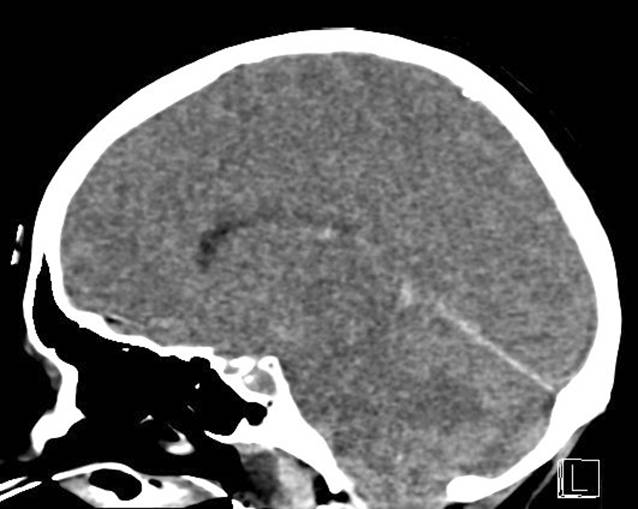

Laborchemisch imponierte eine Leukopenie. Es zeigten sich zentralneurologische Störungen mit weiten, jedoch lichtreagiblen Pupillen, mit horizontalem Bulbuswandern, Bruxismus und tiefer, verlangsamter Atmung. Ein Meningismus konnte nicht festgestellt werden. Die endotracheale Intubation wurde aufgrund des komatösen Zustands mit erloschenen Schutzreflexen notwendig. Es wurde umgehend eine kraniale Computertomographie mit Angiographie durchgeführt. Dabei zeigte sich ein parietookzipitales Hirnödem mit Verplumpung der Gyri (Abb. 2). Dieses Bild ist das typische Korrelat eines posterioren reversiblen enzephalopathischen Syndroms (PRES). Auch elektroenzephalopgraphisch zeigte sich mit biokzipitaler, teils rhythmischer Verlangsamung mit eingelagerten epilepsietypischen Potenzialen ein für das PRES typischer Befund. Als wahrscheinlichste Ursache für ein PRES wurden die bei Wiederaufnahme der Patientin gemessenen supratherapeutischen Serumspiegel von Tacrolimus vermutet.

Abb. 2

Native kraniale Computertomographie, exemplarische Schichten einer sagittalen Rekonstruktion: vasogenes Ödem mit Verplumpung der Gyri in den okzipitalen und parietalen Regionen, suggestiv für ein posteriores reversibles enzephalopathisches Syndrom, postoperativer Tag 39

Erste Diagnose: PRES unter Tacrolimus